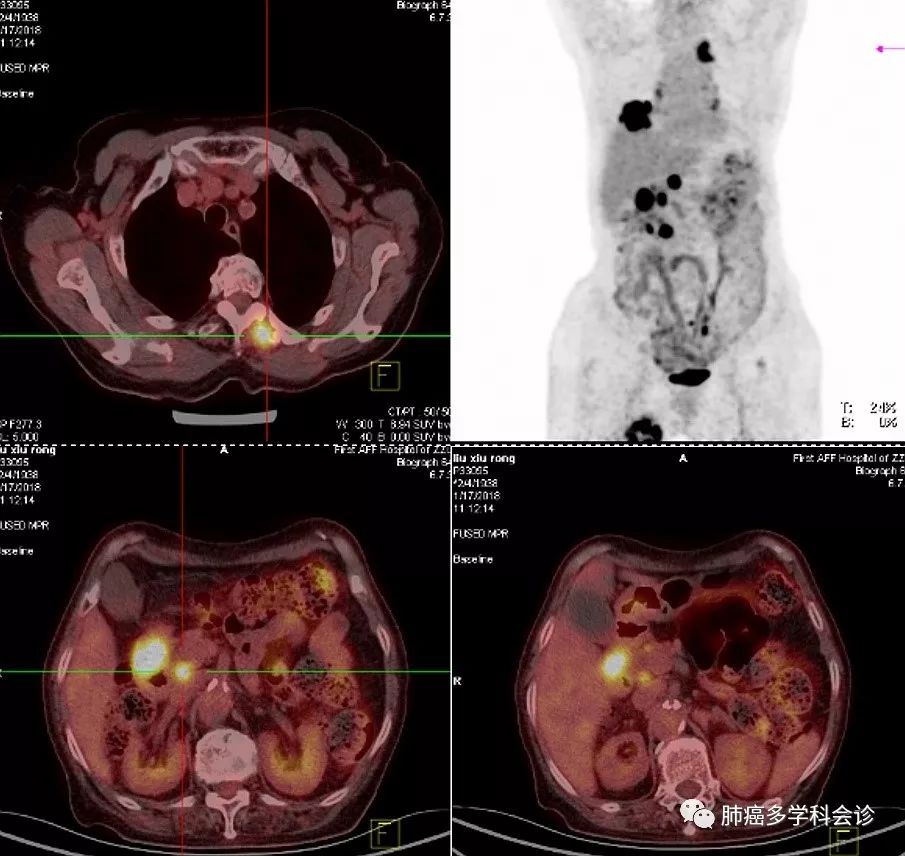

PET-CT示:1.十二指肠降部局部肠壁稍增厚代谢活跃,右肺中叶软组织肿块代谢活跃,考虑恶性病变;右侧顶叶及左侧顶枕叶多个稍高密度结节代谢活跃,腹腔多发肿大淋巴结代谢活跃,T4左侧附件骨质破坏伴软组织肿块代谢活跃,右侧大收肌内低密度团块影代谢活跃,考虑转移。2.右侧结肠旁沟内软组织结节代谢较活跃,考虑良性病变可能。3.右侧丘脑及双侧基底节区软化灶;双侧筛窦及上颌窦炎症。